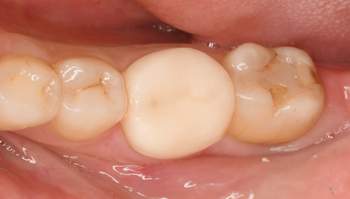

治療前

治療中

治療後

| 治療内容 | 右下6コア形成、仮歯作成、ジルコニアステイン形成 |

| 治療費 | 合計 113,300円(2022年7月現在) 仮歯 3,300円 ジルコニアステイン 110,000円 |

| 治療期間 | 1ヶ月 |

| 治療のリスク・副作用 | 仮歯の期間は仮歯が取れやすくなっている。 天然歯より硬いので噛み合う歯が欠けてしまうことがある。 |